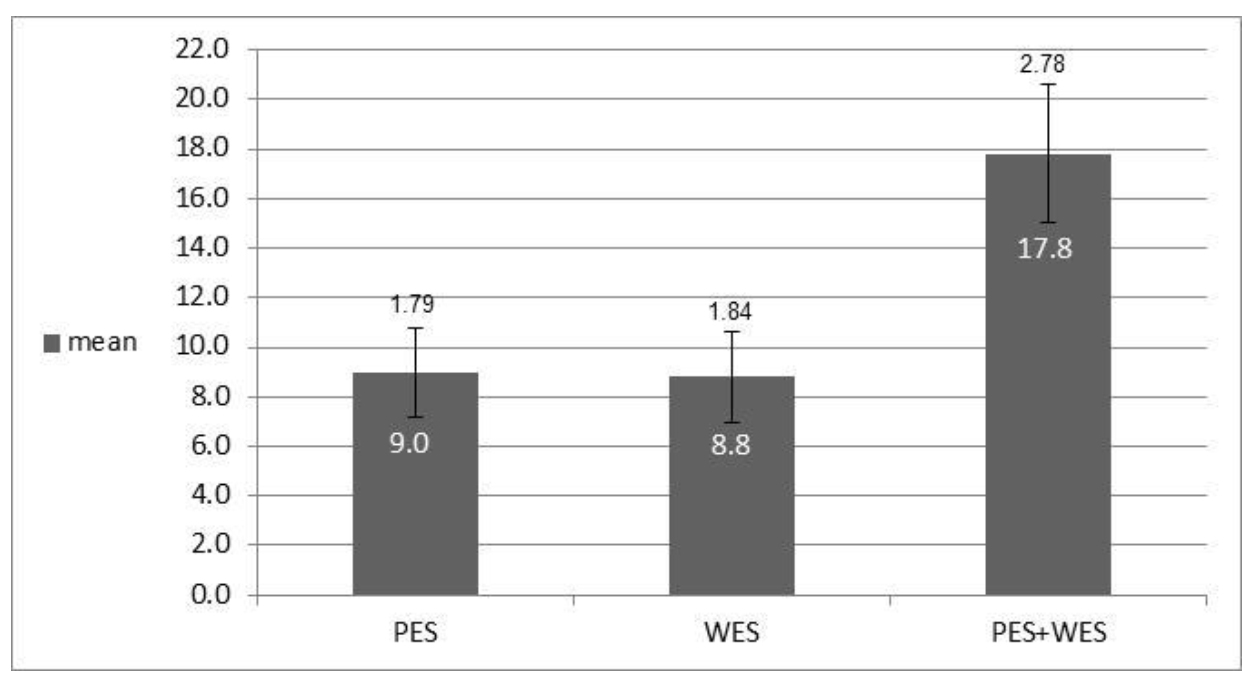

3.5. Analysis of Esthetic Results by Index: PES and WES

| Mean | 1.7 | 1.8 | 1.9 | 1.8 | 1.8 | 9 | 1.8 | 1.8 | 1.8 | 1.7 | 1.8 | 8.8 | 17.8 | |